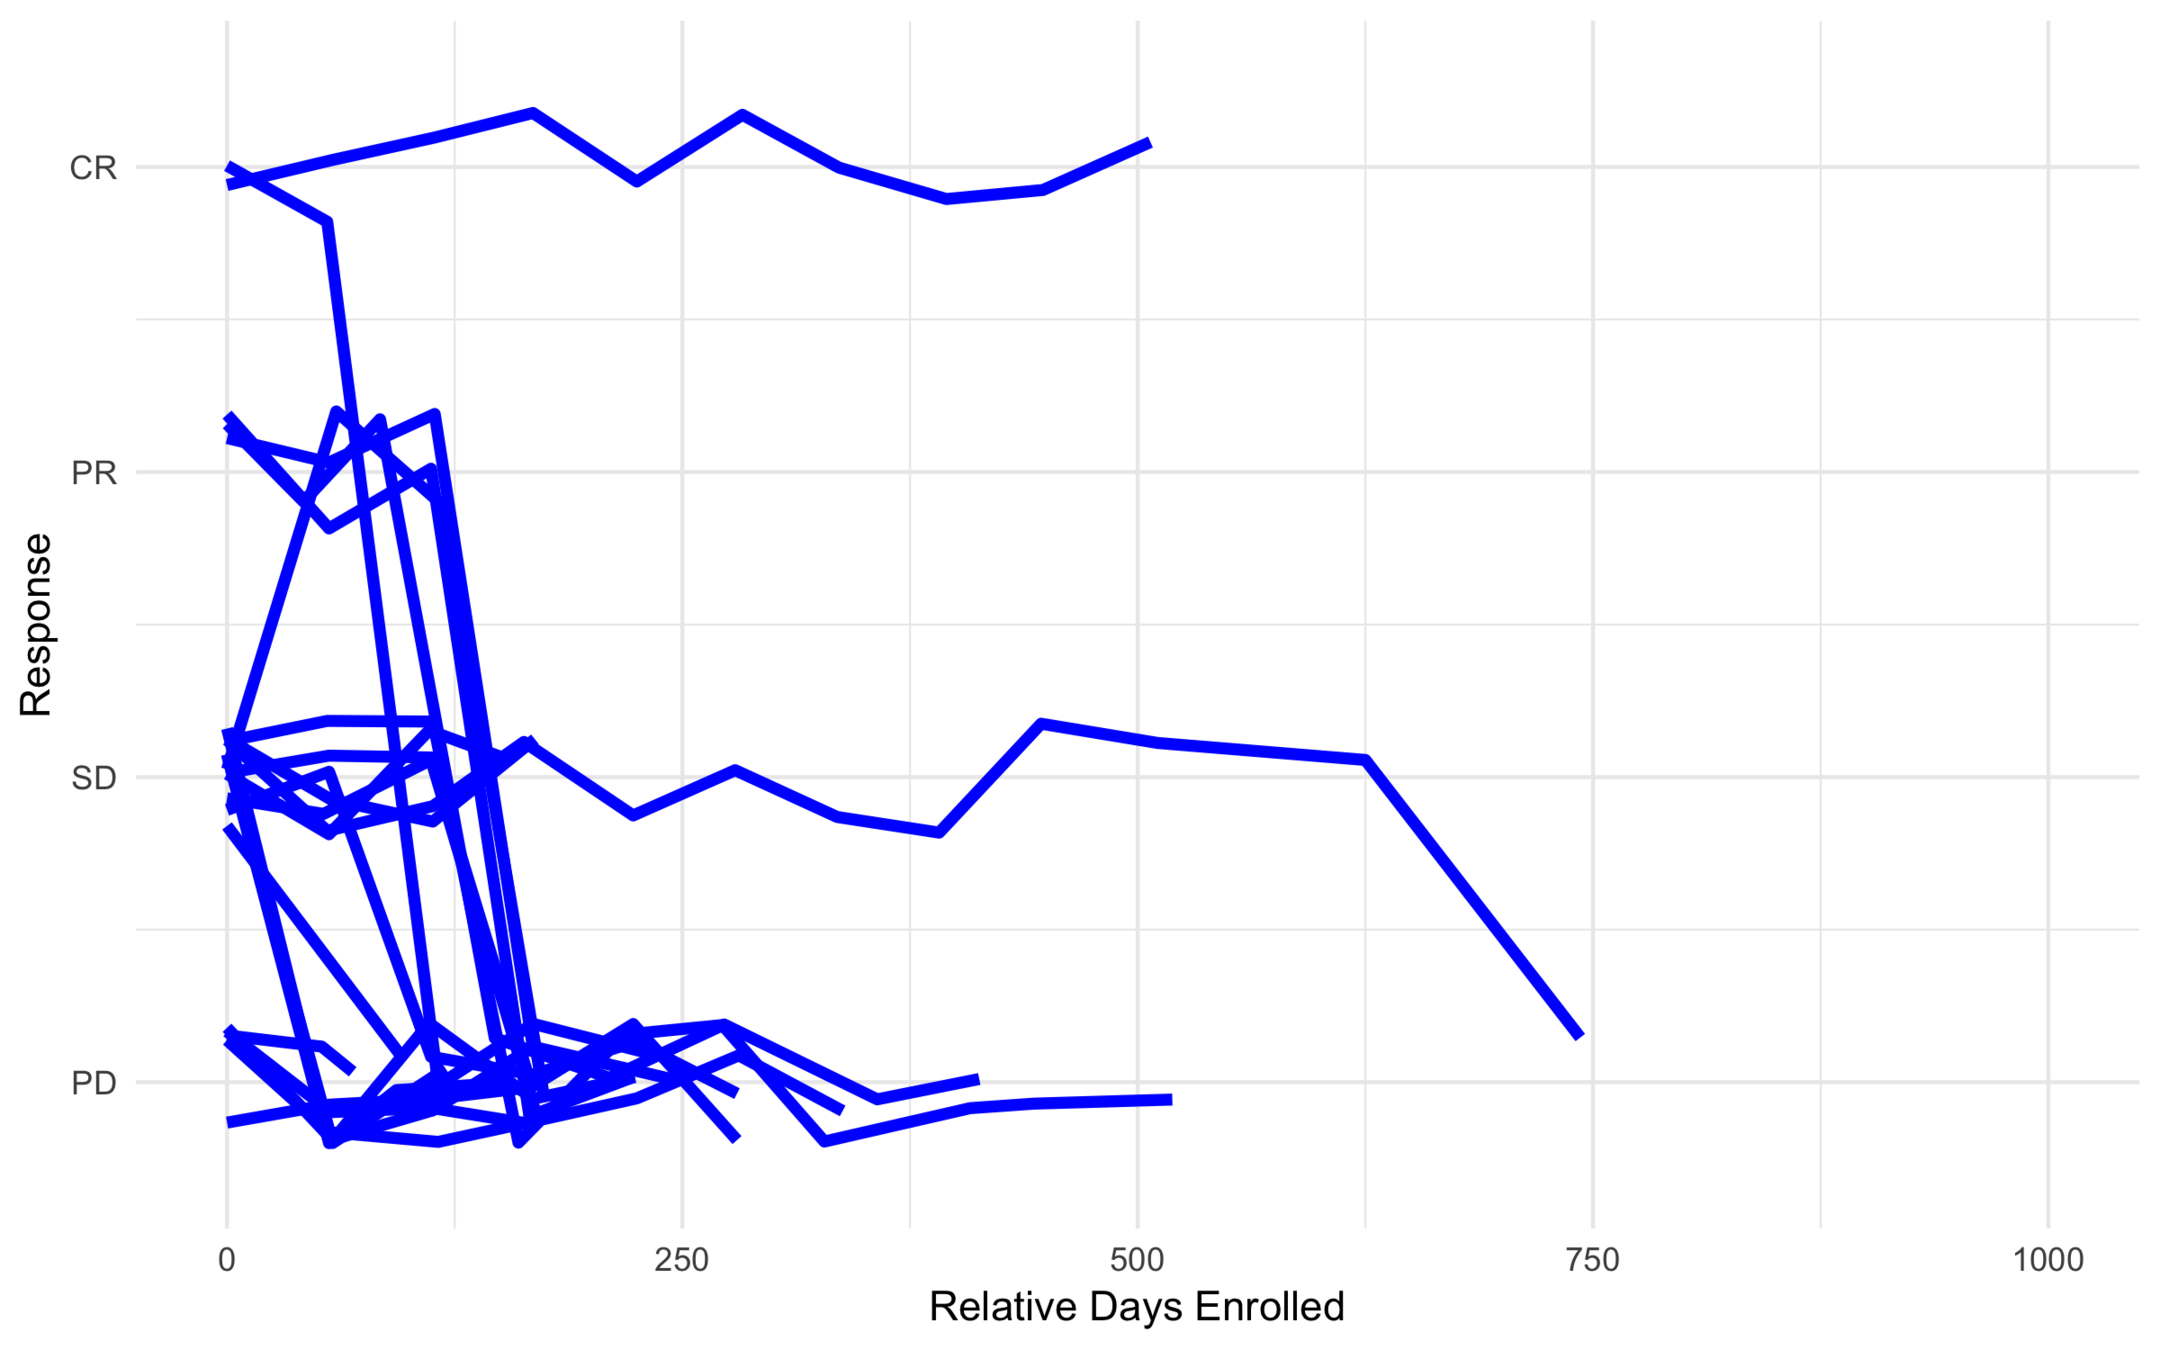

All Trajectories

Low Risk

Intermediate Risk

High Risk

Anonymous Drug 1

Was found to be effective for a certain type of cancer.

Ran into problems with severe toxicity events (449 toxicities out of 607).

Goal was to find subtypes least (or most) likely to have toxicity events.